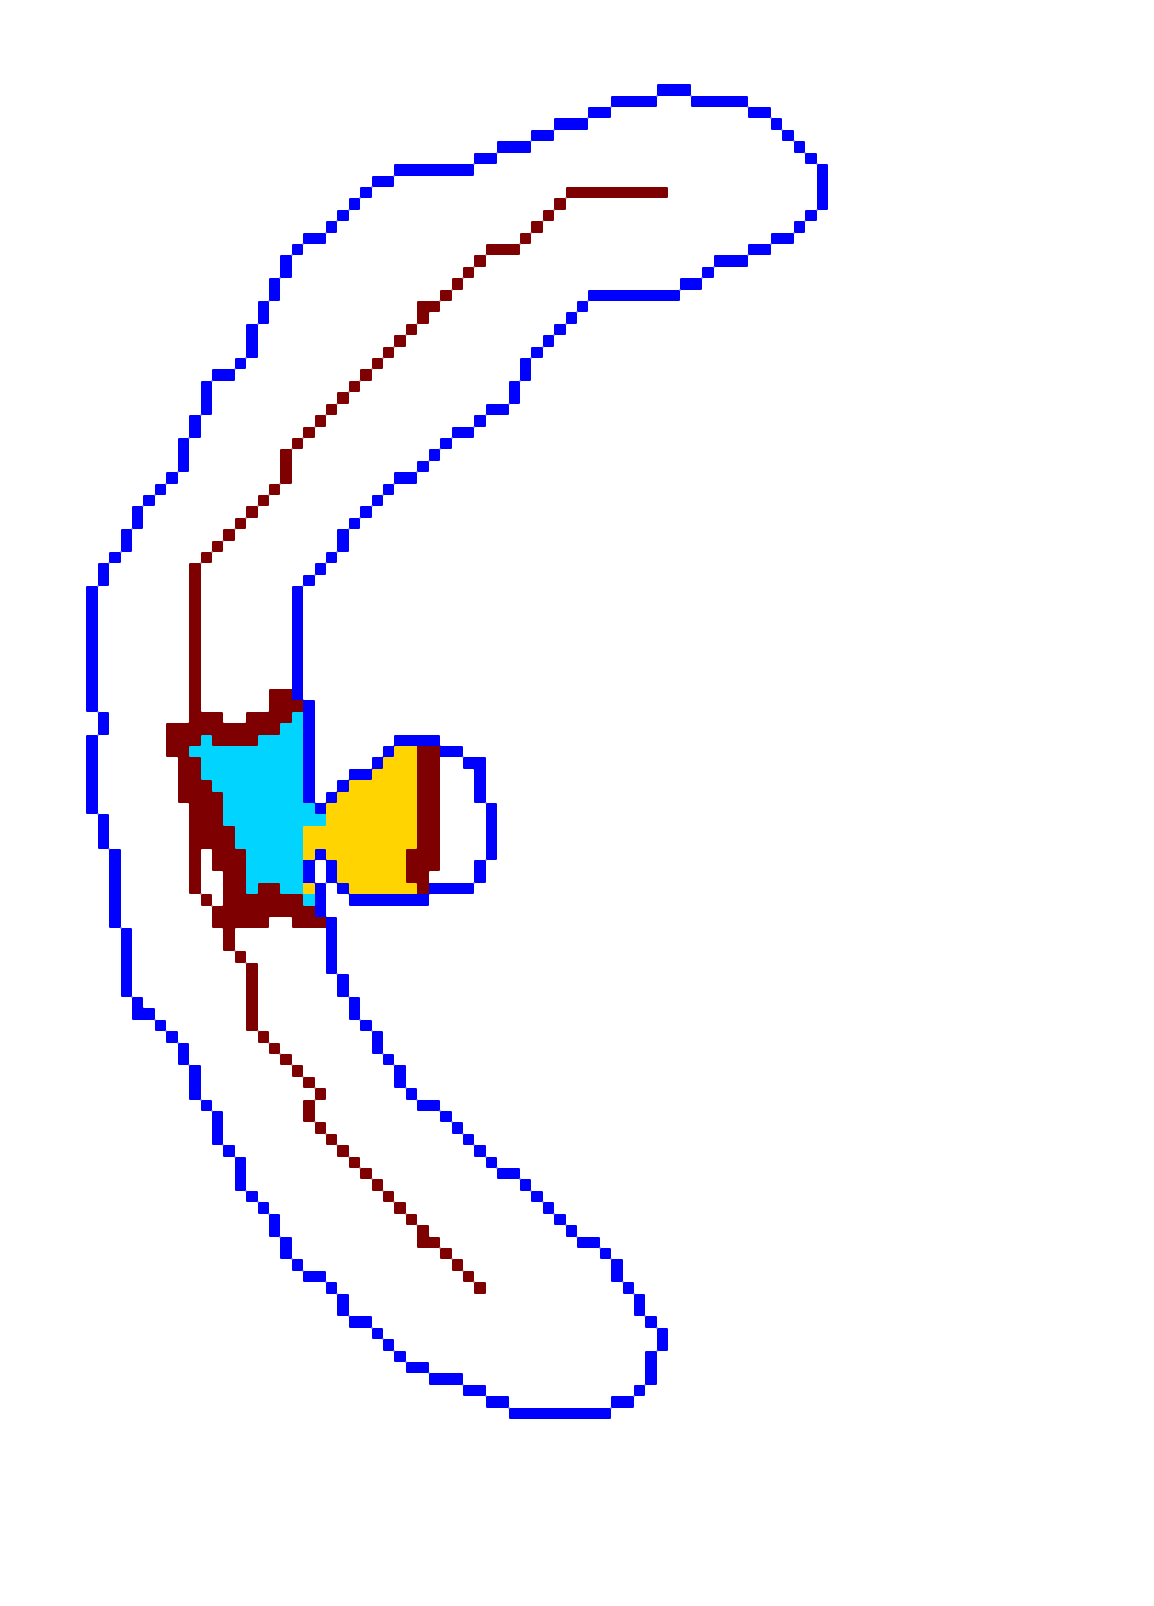

The scalar vesselness responses of both HCP and PC images are determined using the state-of-the-art Frangi filter (FFR) [8], and Optimally Oriented Flux (OOF) [12]. Also, the connected vesselness map (CVM) and the associated tensor field (TF) are synthesized for the same dataset using VTrails. The connectedness of the considered scalar maps is qualitatively assessed and the TF is inspected as proof of concept in section 3.1.

3.1 Connectedness of the Vesselness Map

Fig. 3 shows the connectedness of vessels recovered from state-of-the-art vascular enhancers and curvilinear ridge detectors FFR and OOF together with the proposed CVM for the synthetic HCP and the real PC images.

On the synthetic phantom, FFR shows a fragmented and rough vesselness response in correspondence of irregularly shaped sections of the structure. Also, the response at the bifurcation is not smoothly connected with the branches (triangular loop). Conversely, OOF recovers the phantom connectedness at the branch-point, and the vesselness response is consistent along the tortuous curvilinear section, however ghosting artifacts are observed as the shape of the phantom becomes irregular (C-like) or differs from a cylindrical tube. Also, close convoluted structures, which change scale rapidly in the HCP, produce inconsistent responses of OOF (fig. 3). CVM shows here a strongly connected vesselness response in correspondence of both regular and irregular tubular sections, with local maxima at structures’ mid-line. The connectedness of the structures is emphasized regardless the complexity of the shape, and it resolves spatially the tortuous curvilinear ‘kissing vessels’ without additional ghosting artifacts, despite the smooth profile.

Similar results are observed on the PC dataset: FFR has a poor connected response in the noisy and low-resolution image. Vessels are overall enhanced, however thin and fragmented structures remain disconnected. Overall, the vesselness response is not uniform within the noisy structures, where maximal values are often off-centred. A more consistent response is obtained from OOF, where the connectedness of vessels is improved. Maximal response is observed at the mid-line of vessels, however, noise rejection is poor. CVM strongly enhances here the vessel connectivity. The fragmented vessels of PC have a continuous and smooth response in CVM with higher values and a more defined profile. Large vessels shows solid connected regions with local maxima at mid-line as in OOF. Conversely from OOF, CVM shows improved noise rejection in the background.

The respective tensor fields (TF) synthesized on both HCP and PC show consistent features. The TF’s characteristics are in line with the connectedness of CVM: enhanced and connected vessels are associated with high anisotropy, whereas background areas show a predominant isotropic component.